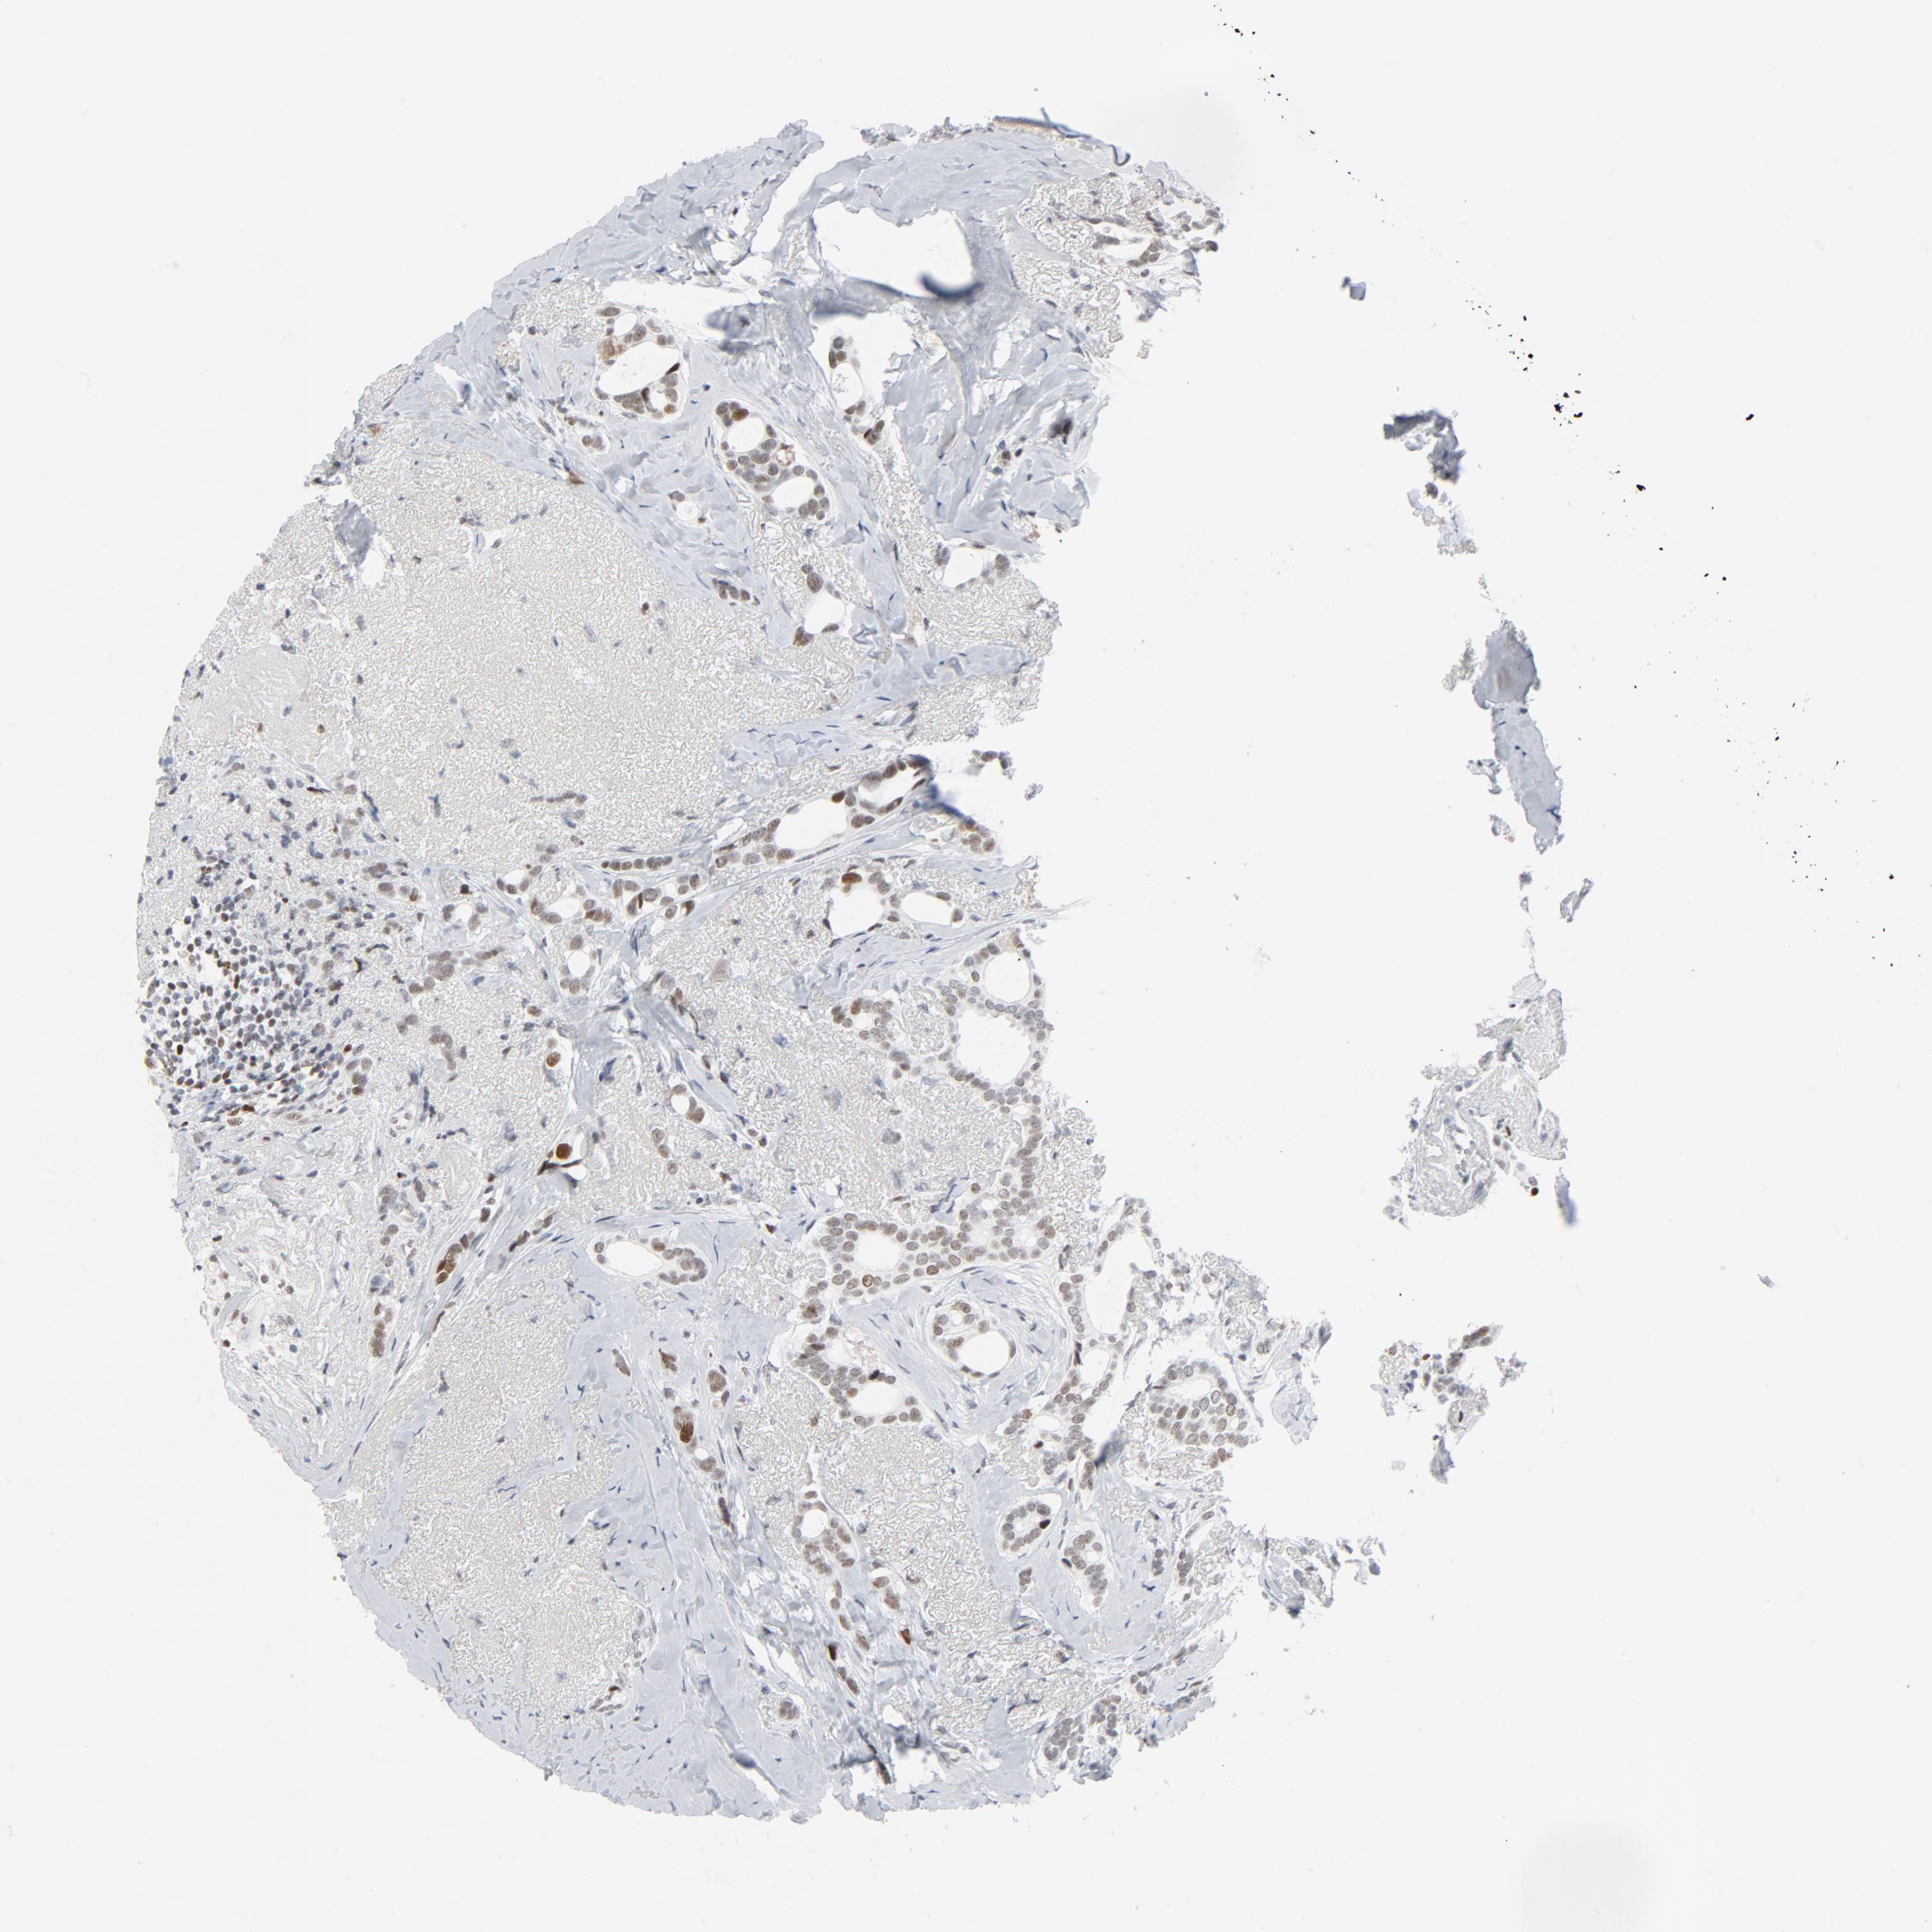

CANCER BREAST CANCER Show tissue menu

BRCA TCGA BRCA VALIDATION PROTEIN EXPRESSION